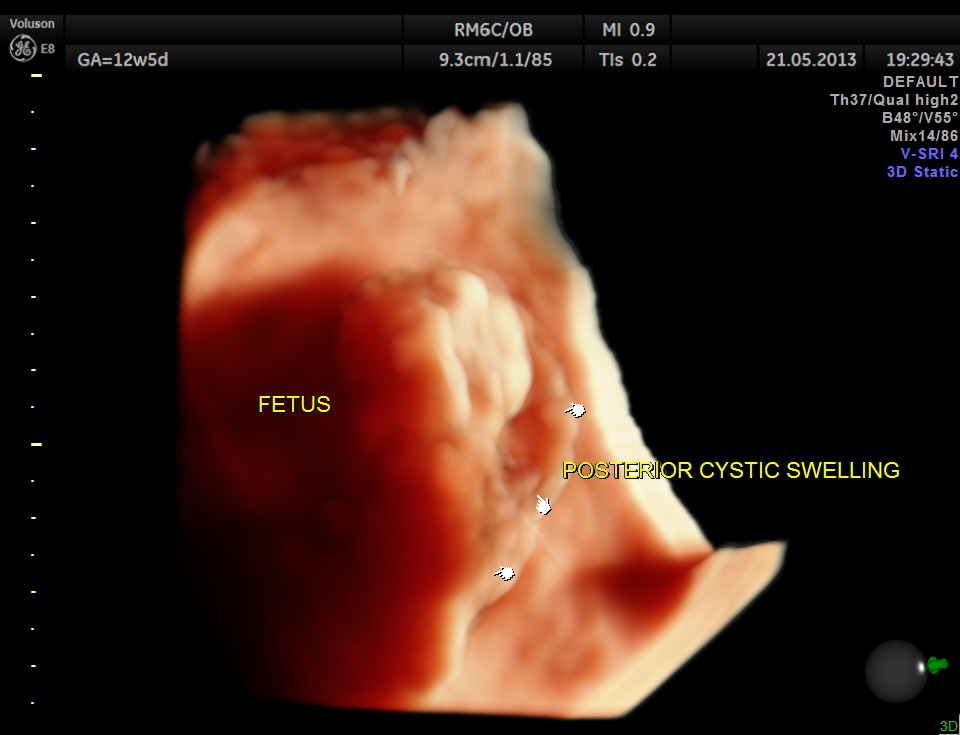

This 23 year old primi gravida, with no history of consanguinity was referred for 2nd opinion for evaluation of cystic swelling of the neck in the first trimester.

the following are some reconstructed images.

The diagnosis offered was cystic hygroma .

Cystic hygroma colli probably represent the most common cause for a neck mass detected prenatally. Other neck masses detectable ultrasonically include cervical meningomyelocele, hemangioma, teratoma, goiter, sarcoma, and metastatic adenopathy. Occasionally, a large cephalocele may mimic a neck mass. In most of these rare cases, polyhydramnios, hydrops fetalis, or other clinical features signal a careful search of the fetal neck.

1. Is the mass unilateral or bilateral, posterior or anterior ?

* most bilateral posterior masses are cystic hygroma colli, especially multicystic masses with a midline septation.